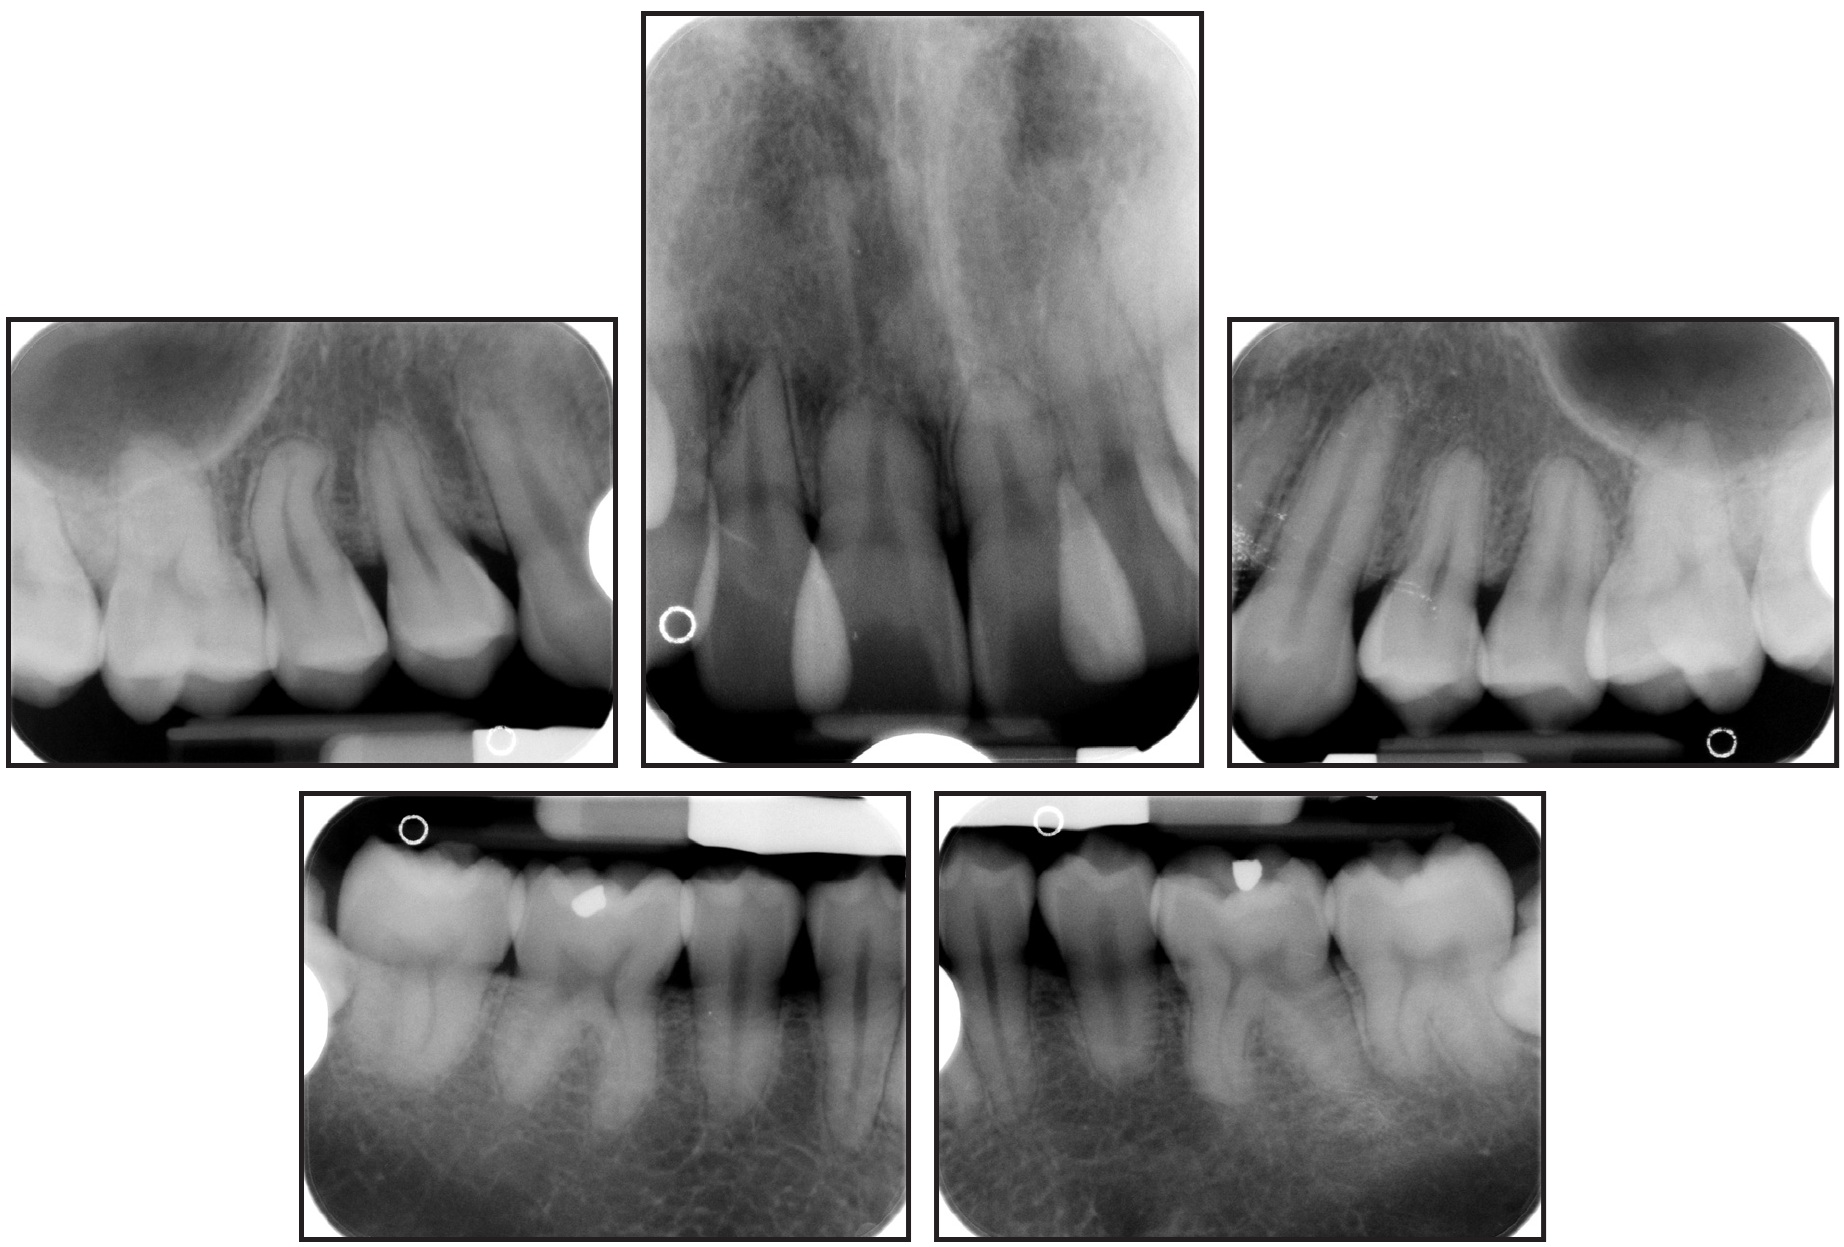

Cephalometric analysis indicated a Class II skeletal base and a convex profile due to a prognathic maxilla. The upper incisors were proclined, and both lips were protruded in relation to the E-line (Table 1). The panoramic radiograph revealed generalized short roots, impacted lower third molars, and a missing upper right third molar.

The root/crown ratios for the first molars, premolars, canines, and upper incisors were calculated as proposed by Lind.1 The most affected teeth were the upper right and left central incisors, with root/crown ratios of .85 and .90, respectively (Table 2).

The patient and his mother reported that no other family members had been diagnosed with short roots. Two brothers of the patient had been previously treated in our clinic and did not present with generalized SRA, but one displayed mild shortening of the premolars—a condition that worsened slightly during orthodontic treatment (Fig. 2).

Fig. 2 Patient’s brother before (A) and after (B) orthodontic treatment.

The upper incisors were substantially retracted, and the lower incisor inclination was reduced. There was improvement in the lip projection, especially the lower, in relation to the E-line (Table 1). The length of the roots—including those of the canines, which underwent active retraction for about 20 months—was basically unchanged from the initial radiograph (Table 2). Because the lower third molars showed significant mesial angulation, they were recommended for removal, along with the unopposed upper left third molar.